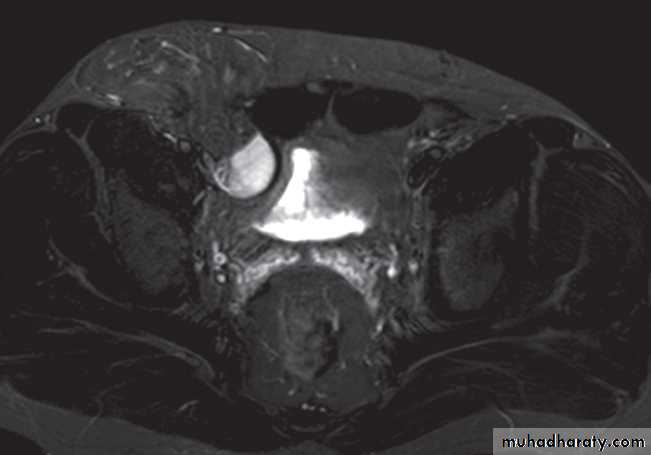

Magnetic resonance imaging is best imaging modality for staging , used to assess early stage prostate cancer in patients being considered for radical surgery or radiotherapy. Tumour in the peripheral zone is seen as a relatively low signal mass within the normal high signal of the peripheral zone on T2-weighted images.

MRI is used to demonstrate extracapsular tumour spread, to show invasion of the seminal vesicles, and to demonstrate possible lymph

node metastases .